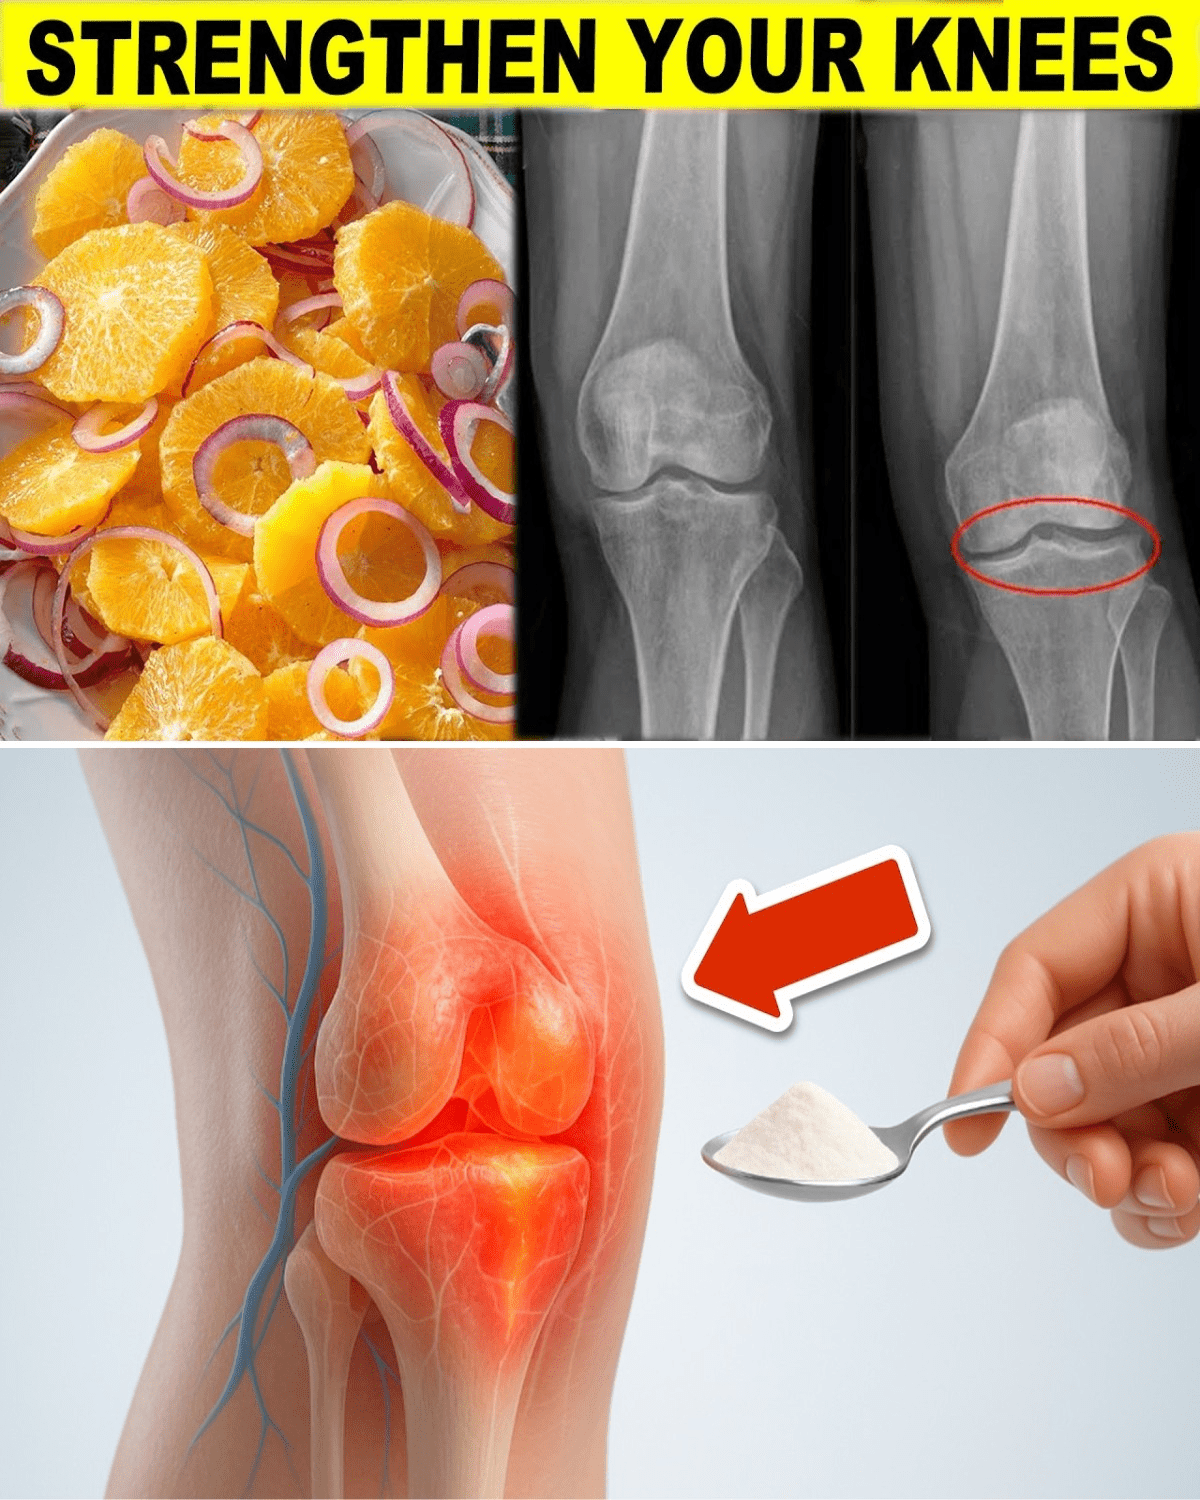

Ever wince climbing stairs, your knees creaking like an old door, wondering if you’ll keep up with life’s pace? Over 30% of adults over 45 report knee pain, often from worn cartilage or weak ligaments, stealing the joy from walks or workouts. What if simple habits could fortify your knees, keeping them limber and strong? These nine easy strategies, backed by science and real stories, could transform your mobility. Ready to step lighter and move freer? Let’s uncover how to strengthen your knees, starting with why they’re crying out for help.

The Silent Strain on Your Knees

Knees bear your body’s weight daily, with cartilage cushioning bones and ligaments stabilizing joints. Aging, inactivity, or excess strain can wear them down, per the American Academy of Orthopaedic Surgeons. Imagine losing hikes with friends because stiffness wins. Up to 25% of older adults face cartilage loss, raising arthritis risks. Curious how to fight back? These nine methods, inspired by Cleveland Clinic insights, offer practical relief. But first, meet someone who turned their pain around.